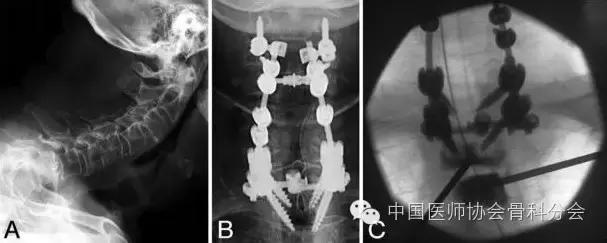

病例2:73岁男性,因严重类风湿性关节炎侵犯颈椎引起半脱位行颈2-胸2后路椎板切除减压植骨融合内固定术,术后6个月出现上胸段皮肤裂开,原因考虑肌肉营养不良和内固定压迫皮肤,后行局部清创、肌瓣转移覆盖术,术后愈合良好。第二次手术术后4个月主诉上胸段疼痛,X检查未见内固定失败迹象,但是发现患者因为类风湿性关节炎需要长期口服糖皮质激素导致的严重的骨质疏松,所以行胸2经椎间盘椎体成形术,胸3行传统的椎体成形术,手术效果良好。

图4. 病例2.A:术前颈椎和上胸椎的侧位片显示颈椎严重的鹅颈畸形和前方的半脱位。B:术后正位片显示后路颈2-胸2钉棒固定和融合。C:术中X线片显示经椎间盘穿刺进入胸2椎体和经椎弓根穿刺进入胸3椎体,并且已经注入骨水泥